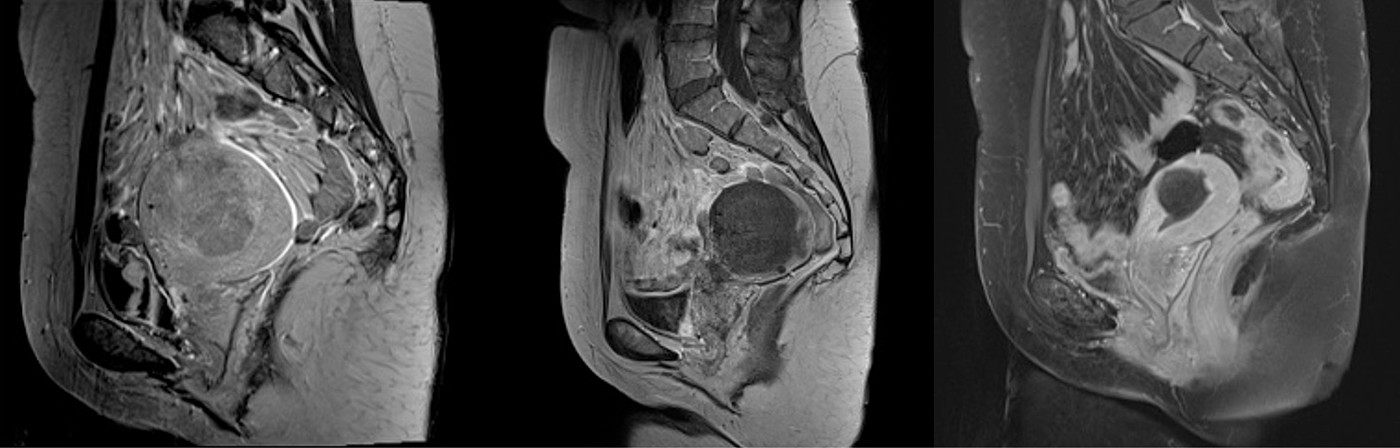

Zur Planung des Eingriffs wird vor der UAE eine Magnetresonanztomographie (MRT) des Beckens mit Kontrastmittel durchgeführt. Dabei werden Größe, Ausdehnung und Lage der Myome erfasst. So lässt sich auch beurteilen, ob Nachbarorgane wie Harnblase, Enddarm oder Wirbelsäule durch die vergrößerten Myome beeinträchtigt werden.

Die UAE erfordert keine Vollnarkose. Die Patientin wird direkt nach der Behandlung auf einer Station der Frauenklinik überwacht und darf schon wenige Stunden nach dem Eingriff wieder aufstehen. Der stationäre Aufenthalt dauert in der Regel vier Tage. Vor der Entlassung wird zur Kontrolle ein erneutes MRT angefertigt und es findet ein Abschlussgespräch mit der Patientin statt, in dem das weitere Vorgehen besprochen wird.

Die Embolisation sorgt für die Schrumpfung der nicht mehr durchbluteten Myome, somit kann sich auch die vergrößerte Gebärmutter verkleinern, was ebenfalls zu einer deutlichen Befundbesserung der Patientin beiträgt.